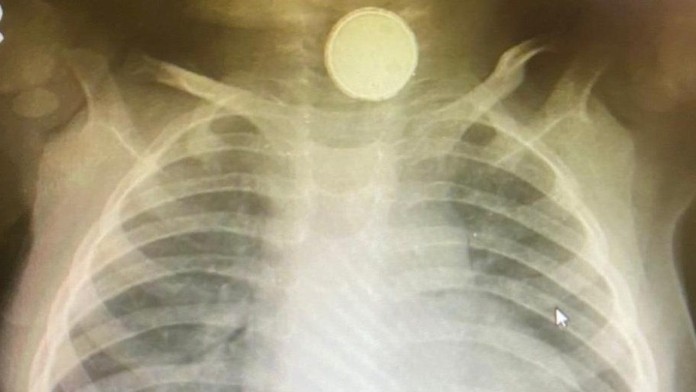

Keď jej však spravili röntgenové vyšetrenie, zostali v šoku. Bábätko malo v pažeráku mincovú batériu.

Momentálne má v hrdle hadicu, ktorá je pomáha ľahšie prijímať potravu. Lekári však nevylučujú, že bude musieť podstúpiť operáciu.